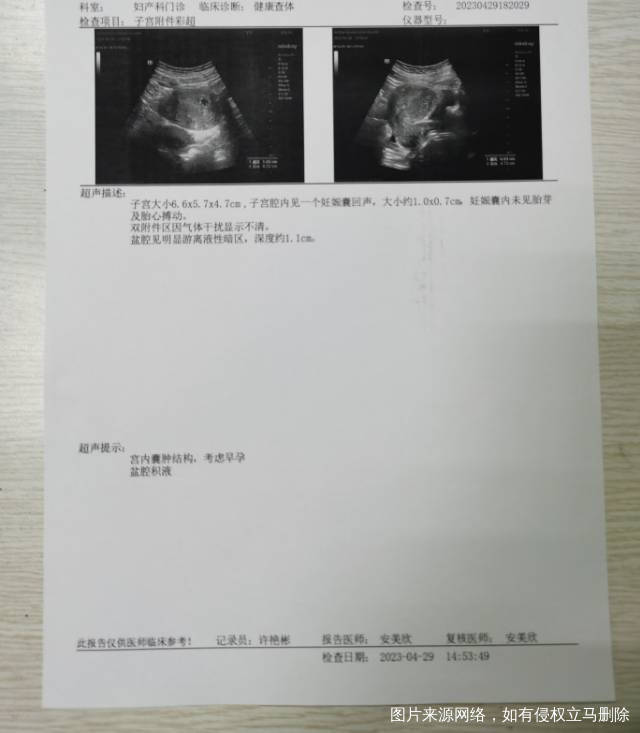

末次月经3.21,麻烦大夫看看彩超,孕囊符合孕周吗?一般几周有卵黄囊?